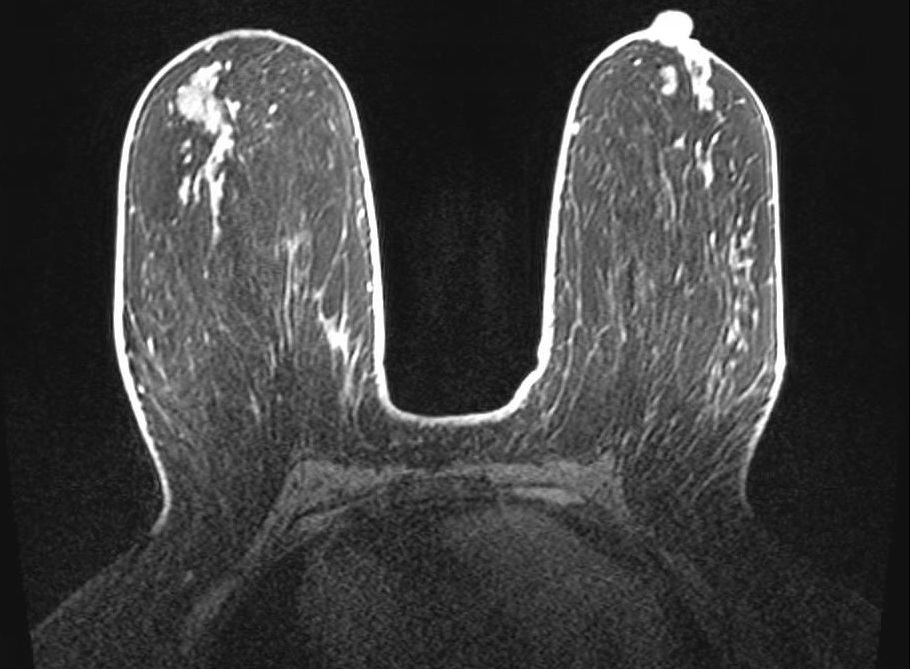

Fat Sat / B0 - Peripheral

Peripheral fat suppression failure due to B0 inhomogeneity. Axial fat-saturated T1-weighted image shows characteristic failure at the periphery of the FOV with preserved central suppression. This center-frequency mismatch pattern reflects the inability of volume shimming to compensate for field variation at the magnet periphery, and is a common pitfall in larger patients or those with asymmetric body habitus.